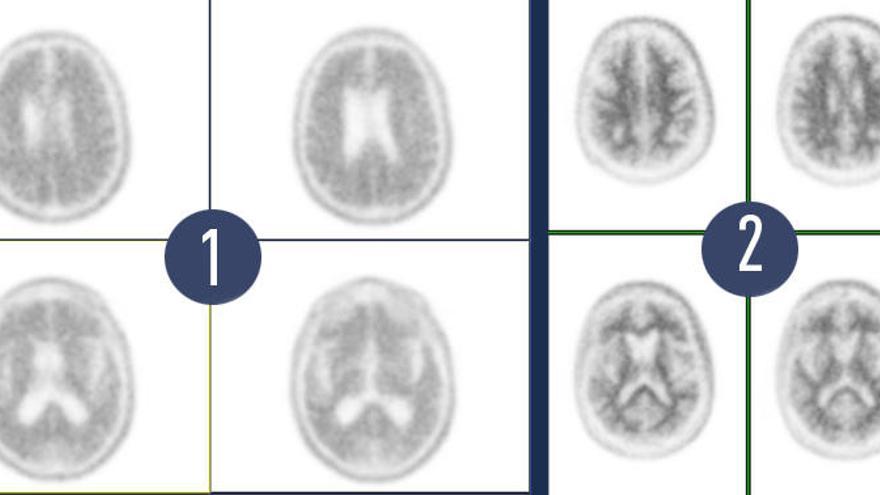

Esta prueba supuso una revolución diagnóstica en torno a la enfermedad de Alzheimer pues, hasta entonces, los distintos estudios diagnósticos de imagen RM y TAC desvelaban la muerte neuronal o la pérdida de volumen. “Antes que se produzca esta pérdida de volumen, hay una disfunción neuronal que los estudios PET con fluorodesoxiglucosa permiten evaluar. Pero, incluso antes de la disfunción neuronal, se produce en el cerebro un depósito de las placas de amiloide, que puede ser estudiado con PET”, aclara el Dr. Pablo Sopena.

La PET de amiloide se convertía así en la primera y única herramienta diagnóstica aprobada por la Unión Europea que muestra la presencia o ausencia de placas amiloides, suponiendo una auténtica revolución diagnóstica en torno al Alzheimer.